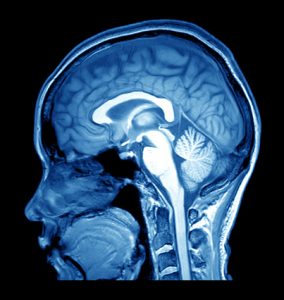

Most people know that experiencing a stroke is serious and perhaps even life-threatening, but what most people don’t understand is why they happen. There are two kinds of stroke: hemorrhagic and ischemic. Both cause brain tissue to lose its blood supply, risking cell death.

Most people know that experiencing a stroke is serious and perhaps even life-threatening, but what most people don’t understand is why they happen. There are two kinds of stroke: hemorrhagic and ischemic. Both cause brain tissue to lose its blood supply, risking cell death.

Hemorrhagic strokes are less common, making up about 15 percent of all stroke cases. They can either be due to a brain aneurysm rupture or a weakened blood vessel leak. Brain damage occurs as blood spills into or around the brain, creating swelling and pressure.

Hemorrhagic stroke has a 30 to 67 percent mortality rate and is the main cause of disabilities among adults. Half of hemorrhagic stroke victims die within the first two days.

The researchers believe that most victims die due to secondary damage occurring from the toxicity of iron caused by the breakdown of red blood cells, leading to excess free radicals and inflammation. This reaction is caused by white blood cells and is called neutrophils.

When blood is released into the brain, neutrophils arrive at that point even if there are no signs of infection. If they remain, not being removed by other immune cells, they will release their destructive contents into the brain and worsen brain injury.